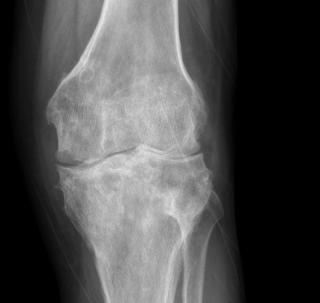

остеоартрит.